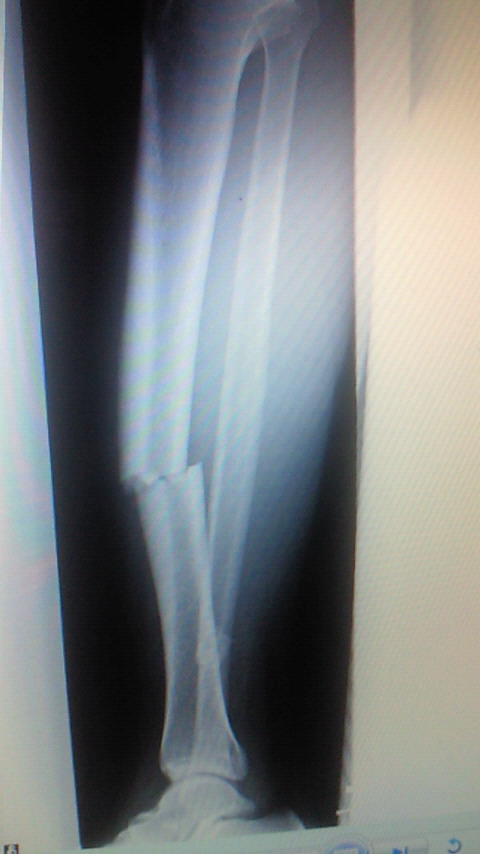

左が術前で右が術後です。(;^_^A

先生にお願いしましてレントゲンをゲットしました!(o^o^o)

右が術前で左が術後です。(@_@;)

腓骨(細い骨)は折れたままです。